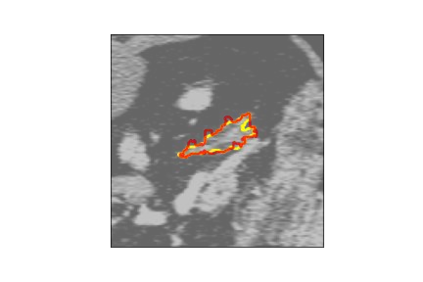

The human annotations are imperfect, especially when produced by junior practitioners. Multi-expert consensus is usually regarded as golden standard, while this annotation protocol is too expensive to implement in many real-world projects. In this study, we propose a method to refine human annotation, named Neural Annotation Refinement (NeAR). It is based on a learnable implicit function, which decodes a latent vector into represented shape. By integrating the appearance as an input of implicit functions, the appearance-aware NeAR fixes the annotation artefacts. Our method is demonstrated on the application of adrenal gland analysis. We first show that the NeAR can repair distorted golden standards on a public adrenal gland segmentation dataset. Besides, we develop a new Adrenal gLand ANalysis (ALAN) dataset with the proposed NeAR, where each case consists of a 3D shape of adrenal gland and its diagnosis label (normal vs. abnormal) assigned by experts. We show that models trained on the shapes repaired by the NeAR can diagnose adrenal glands better than the original ones. The ALAN dataset will be open-source, with 1,594 shapes for adrenal gland diagnosis, which serves as a new benchmark for medical shape analysis. Code and dataset are available at https://github.com/M3DV/NeAR.